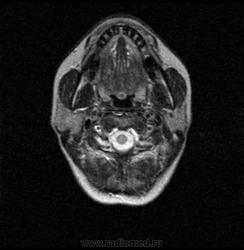

06.06.2011 МРТ - головы и шеи.

Пацентка 36 лет, с жалобами на припухлось в околоушной области справа.

В глубокой доле  правой околоушной железы  на фоне неизмененной паренхимы зона  гетерогенного по Т2, гипоинтенсивного по Т1  с единичными гиперинтенсивными включениями.При контрастировании- накопление контраста диффузное неоднородное и по периферии.Рискну предположить злокачественное образование ( аденокарцинома) с низкой степенью злокачественности( есть капсула, экспансивный рост).Сильно не расстреливайте.

Проблема в том, что перед челюстно-лицевым хирургом стоит распространенность любого объемного процесса, в данном случае все упирается в возмможную травму лицевого нерва и конечно же с дальнейшим его парезом, а ведь женщина  еще молодая. Образование имеет тонкостенную оболочку, по структуре неоднородно, с наличием кальцината, при этом МР-сигнал от окружающих анатомических структур(как костных так и мышечных) не изменен, т.е. об инфильтративном росте речи не идет, в какой то степени доброкачественное. В конкретном случае лицевой нерв с ретромандибулярной веной просто несколько оттеснен.

По гистологии аденома околоушной слюнной железы, но после удаления пока сохраняется парез лицевой мускулатуры, возможно временный.